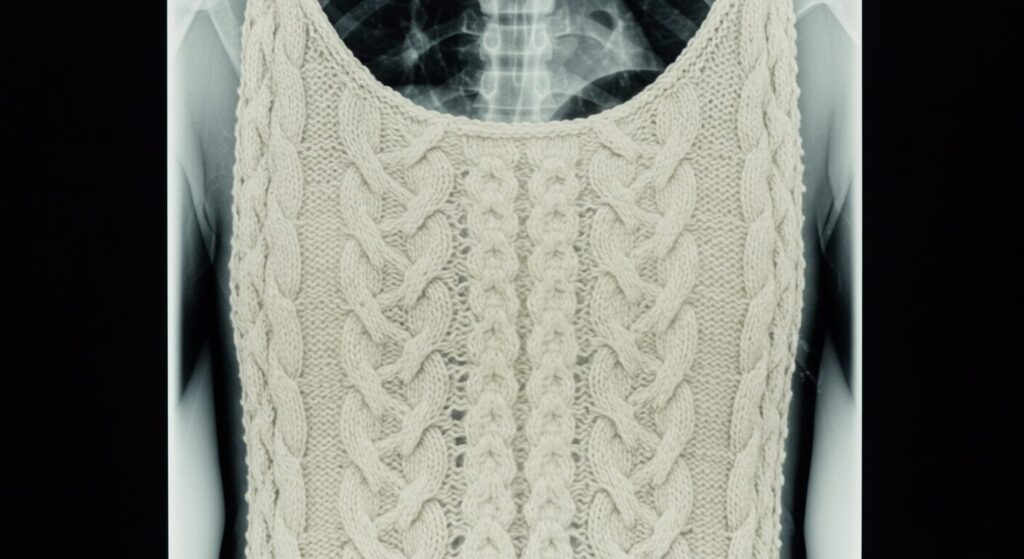

2. なぜ「ニット」はレントゲン検査で要注意なの?意外と知らないその理由

ニットって、金属が入ってるわけじゃないし、大丈夫じゃないの?

そう思われた方も多いはず。私も以前はそう思っていました。でも、実はここにレントゲン検査の「落とし穴」が潜んでいるのです。この章では、なぜあなたの愛用ニットが検査の邪魔になるのか、その科学的な理由をわかりやすく解説していきますね。

では、なぜニットが問題になるのでしょう?それは、「厚み」と「密度」がキーワードです 。ニットは、その編み方や素材(ウール、アクリルなど)によっては、見た目以上に「厚手」になりますよね 。この厚手さや、繊維がぎゅっと詰まった密度が高い部分は、X線を吸収しやすくなってしまうのです 。

さらに、ニットにはもう一つ厄介な特徴があります。それが「アーチファクト(人工物)」と呼ばれる現象です。これは、画像上に不必要な影やムラができてしまうこと。ニットは均一な布地とは違い、編み目や素材の不均一さがありますよね。この不均一さが、X線画像上で「ムラ」や「不均一な影」として現れることがあるのです 。

このアーチファクトが何が問題かというと、診断の妨げになることです 。例えば、本来の病変と見間違えたり、あるいは病変の識別の邪魔になる「ノイズ」として作用したりする可能性があります 。医師は、病気を見つけるために非常に微細な影の変化まで見極めようとします。そんな時に、服の影が「偽の病変」のように見えてしまっては、正確な診断が難しくなってしまいますよね 。

多くの医療機関がこの「見落としリスク」を強調しているのは、過去に実際にこのような服装が原因で、診断に支障が出た経験があるからかもしれません。だからこそ、たかがニット、されどニット。あなたの健康を守るために、適切な服装選びが本当に大切なのです!